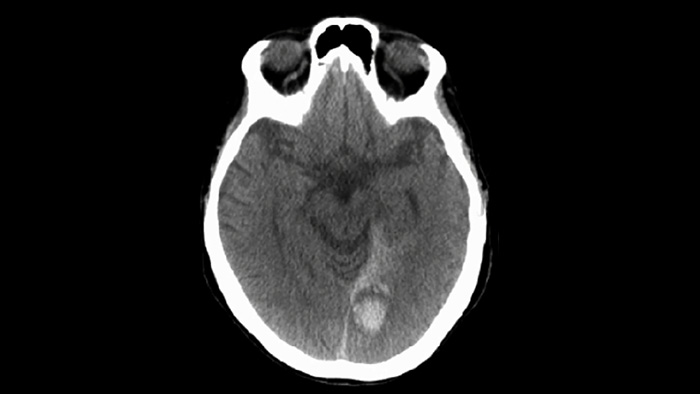

Utilize a imagiologia de SmartCT Soft Tissue no conjunto Neurovascular para verificar o sucesso do tratamento e identificar hemorragias.

A tecnologia ClarityIQ reduz a dose do paciente em 75% em DSA Neuro*, ao mesmo tempo que mantém uma qualidade de imagem equivalente, em comparação com um sistema sem ClarityIQ para suportar uma população de pacientes mais ampla. A sua compensação automática do movimento remove os artefactos causados pelos movimentos e do crânio que são fundamentais ao colocar pequenos dispositivos na base do crânio.

A tecnologia ClarityIQ reduz a dose do paciente em 75% em DSA Neuro2, ao mesmo tempo que mantém uma qualidade de imagem equivalente, em comparação com um sistema sem ClarityIQ. A sua compensação automática do movimento remove os artefactos do crânio e do movimento que são fundamentais ao colocar pequenos dispositivos na base do crânio.